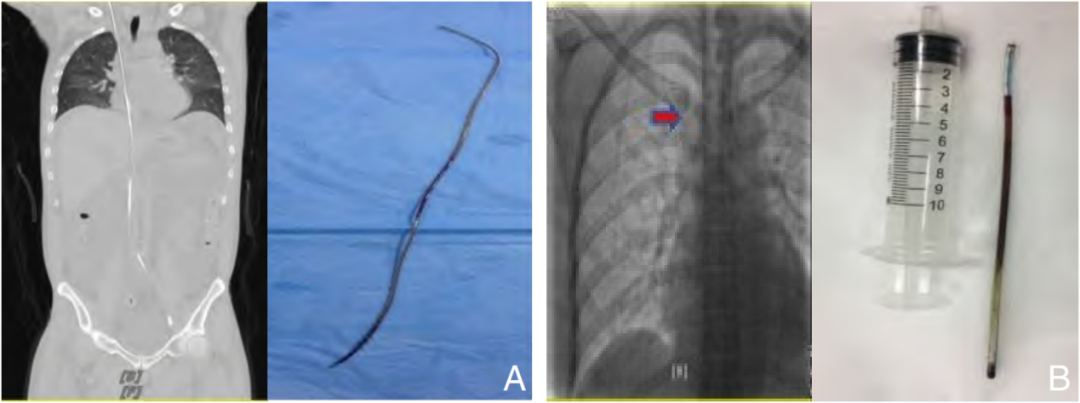

患者医源性血管内异物术前、术后照片。

A为导丝异物(腔静脉);B为静脉输液港导管断裂(上腔静脉)。

图源/《中国普通外科杂志》